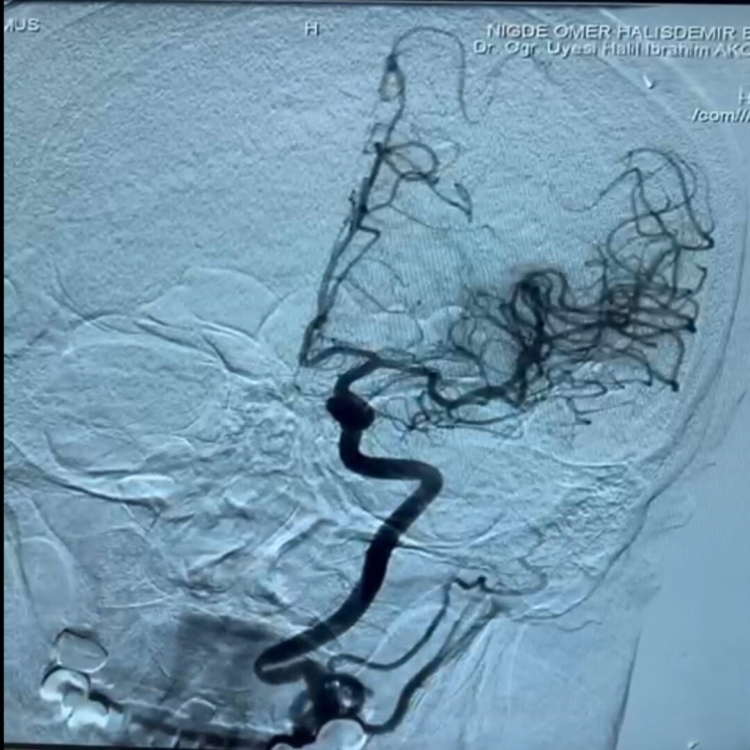

Niğde Ömer Halisdemir Üniversitesi Eğitim ve Araştırma Hastanesi Nöroloji Uzmanı Dr. Öğretim Üyesi Halil İbrahim Akçay, 2024 yılından bugüne 1 yılda toplam 100 hastanın tedavi edildiği merkezimiz hakkında bilgi verdi. İnmenin beyin damarlarında tıkanma ya da kanama sonrası felç ve ölüme neden olan önemli bir sağlık problemi olduğunu söyleyerek tüm dünyada erişkin yaştaki ölümlerin ikinci en sık nedeninin inmeden kaynaklandığını, erişkin yaştaki nörolojik engelliliğin ise en sık nedeninin inmeden kaynaklandığını belirtti. İnmelerin yüzde 80 gibi büyük bir kısmında neden, damar tıkanıklığıdır. Diyabet, obezite oranı ve yaşam süresinin artması gibi faktörler nedeniyle inme sıklığının daha da artması beklenmektedir. İnme merkezimizde, inme ile başvuran hastalarımıza erken dönemde kateter anjiyografi yöntemi ile pıhtı çıkarma ve damardan kan sulandırıcı tedavilerini 7/24 esasında uyguluyoruz. Bu nedenle inmede tedavide zaman kaybını önlemek için 112 sağlık hizmetlerimiz, hastane acil servisimiz, inme merkezinde görevli hekimler inme merkezi personellerimiz koordineli bir şekilde çalışma yapmaktadırlar. Hepsine teşekkürlerimi iletiyorum.” dedi.

Son model teknolojik cihazlarla donatılan ve alanında uzman nöroloji hekim ve personellerin görev yaptığı merkezde, beyin damarlarında tıkanma ya da kanamaya bağlı olarak ortaya çıkan, bazen ölüme bile yol açabilen damar tıkanıklıklarının başarılı bir şekilde tedavi edildiğini belirtti. Felçle gelen ve felç kalma riski olan hastalara 7/24 esasında tedavi imkânı sunan merkezin hem Niğde'ye hem de Niğde dışından gelen hastalara şifa dağıttığını aktaran Doğan, ''Nevşehir, Aksaray gibi bölge içi pek çok şehirden hasta geliyor. Bunun için tüm ekibe ve emeği geçen herkese teşekkür ederim'' şeklinde konuştu.